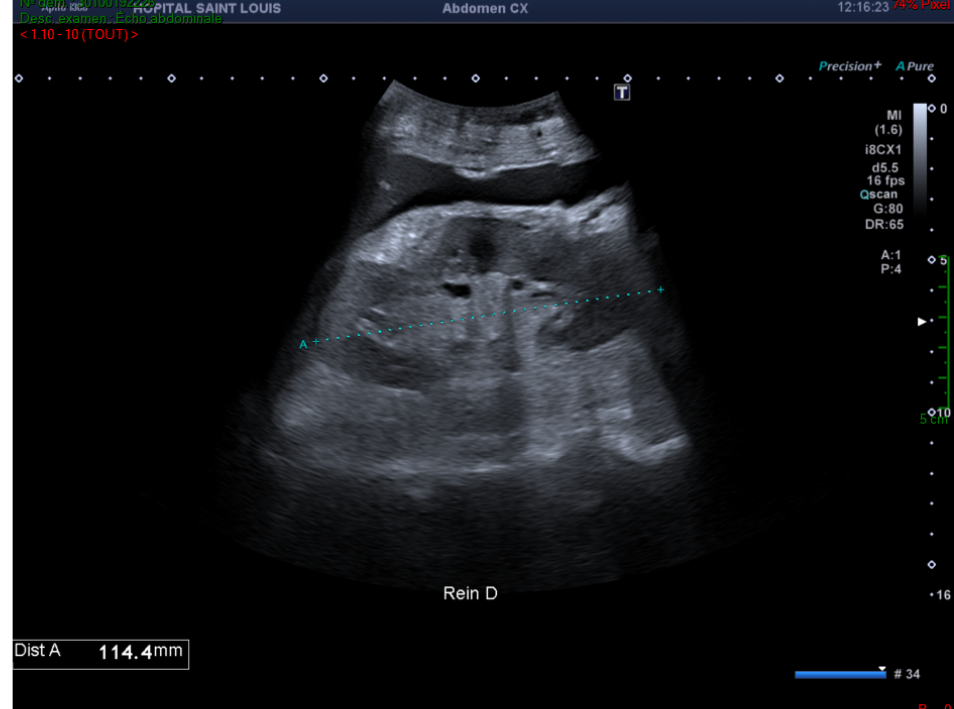

Une dilatation des veines hépatiques avec un diamètre mesuré à 16mm.

Le diamètre maximal d'une veine sus-hépatique mesuré avant son entrée dans la veine cave  inférieure est de 10 mm .

Une valeur plus élevée indique une dilatation, elle est typiquement retrouvée dans les insuffisances cardiaques droites.